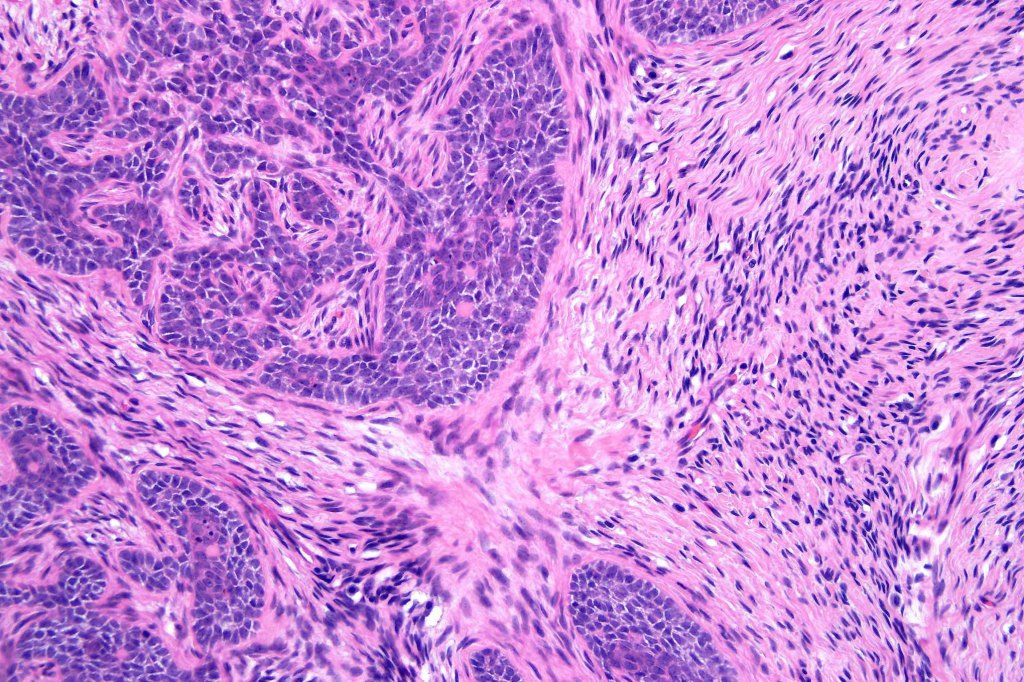

•Variably sized but generally large, basophilic tumor nodules composed of small uniform basaloid cells with minimal cytoplasm

•Variable mitotic activity, can be brisk

•No pleomorphism or abnormal mitoses

•Peripheral palisading but no retraction artifact or stromal mucin deposition

•A rich fibromyxoid mesenchymal stroma with variable papillary mesenchymal bodies (sometimes these are absent)